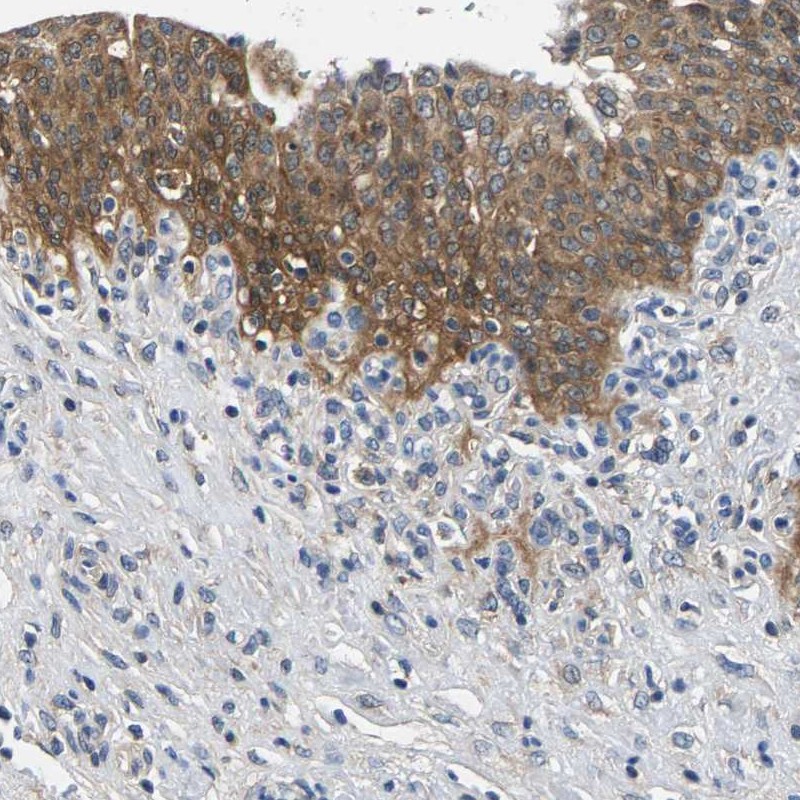

Immunohistochemical staining of human urinary bladder shows moderate cytoplasmic positivity in urothelial cells.